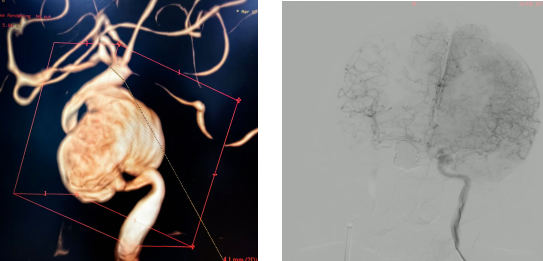

患者入院后进一步完善检查,许刚副主任医师发现其右侧颈内动脉海绵窦段存在巨大动脉瘤,分为两个子囊,大小约40×38mm,瘤体大部分突入海绵窦及蝶窦。患者血管异常迂曲,载瘤动脉近端及瘤颈部狭窄。结合患者有放疗史,考虑该巨大动脉瘤为放疗后继发,假性动脉瘤可能性大。

手术中,许刚副主任医师、僧志远主治医师先在局部麻醉下为患者行BOT试验,采用球囊闭塞患侧载瘤动脉近端。患者肢体活动及语言功能未见异常,前交通动脉开放代偿良好。为进一步确认,在麻醉医师配合下将患者血压降低20%,继续观察20分钟,患者仍无明显不适,BOT试验确认通过。随后在气管插管全麻下行颅内动脉瘤栓塞及载瘤动脉闭塞术,手术顺利。术后患者正常苏醒,四肢活动及语言功能正常。

图1:术前3D 图2:术后造影